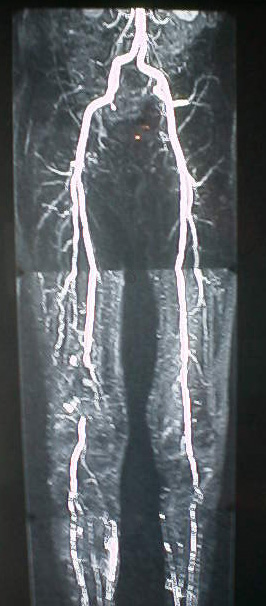

Magnetic resonance (MR) is a rapidly developing noninvasive imaging modality. It is currently used in a variety of diagnostic imaging applications, including components of the nervous system and musculoskeletal system. The following aortogram MR image was obtained from http://www.newmri.com/aortogram.htm